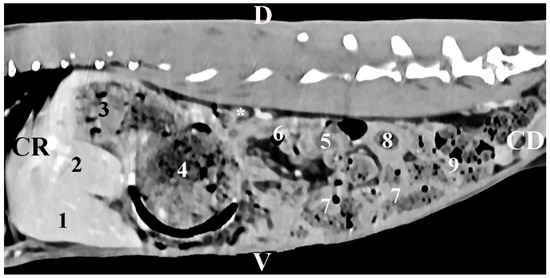

The transverse post-contrast CT anatomical investigation at the level of the 12th thoracic vertebra (Th12) gave complete information about the topographic location and shape of the right adrenal gland. The latter was a retroperitoneal soft tissue finding located in the intrathoracic part of the abdominal cavity. The gland was localized on the right of the median plane, in the dorsal abdominal quarter. It was detected dorsally and in close proximity to the contrast-enhancing v. cava caudalis, the aorta abdominalis, and the liver. The borders of the right adrenal were sharply delineated, which defined it as an ellipse-shaped structure. The soft tissue attenuation of the gl. adrenalis dextra was relatively lower than that of the right liver lobe (Figure 1).

Figure 1. Transverse CT post-contrast anatomical study of the rabbit abdomen at the level of Th12. L—left; R—right. (1) aorta abdominalis; (2) v. cava caudalis; (3) right adrenal gland; (4) lobus hepatis dexter; (5) caecum; (6) duodenum; (7) ileum; (8) corpus ventriculi; (9) fundus ventriculi.